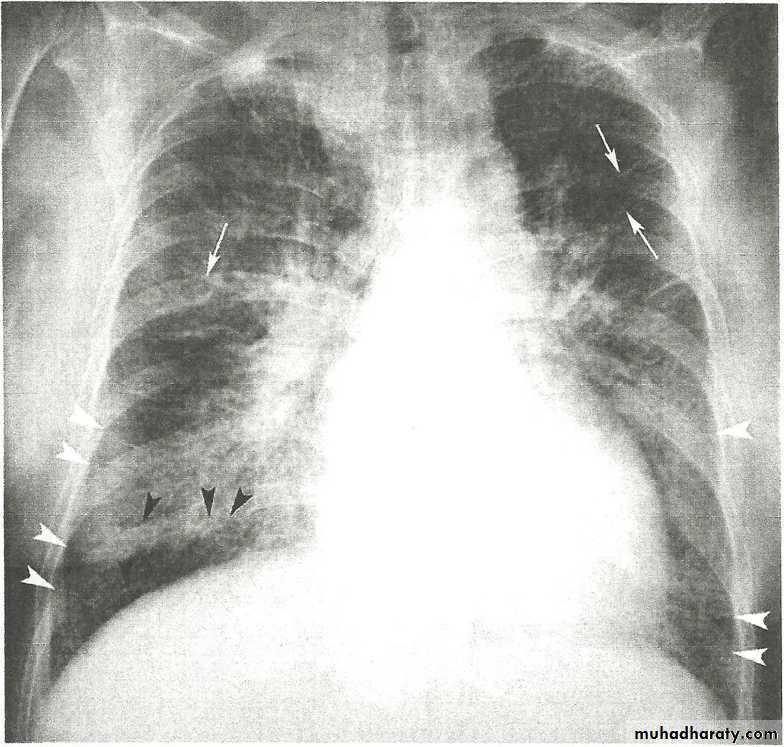

• Alveoiar oedema (‘Bat’s wings’)

• Kerlev B lines (interstitial oedema)• Prominent upper lobe vessels

• Cardiomegaiy

• Pleura

• effusionKerley A lines (Arrows), Kerley B lines (arrowheads)